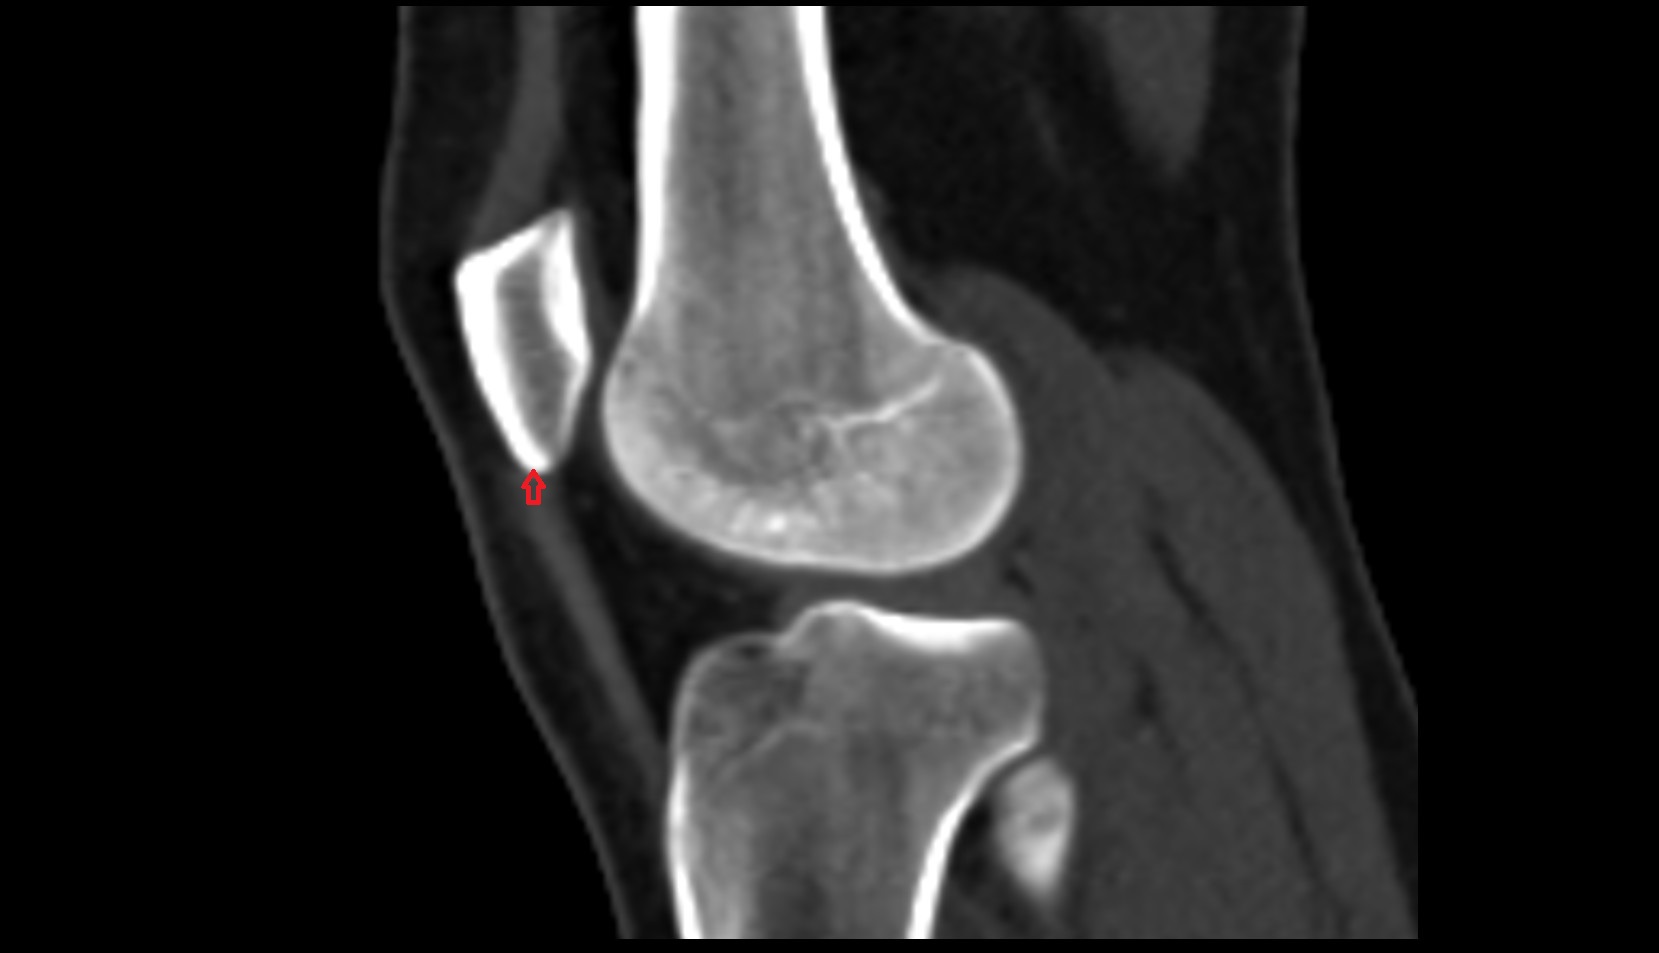

- Knee Joint